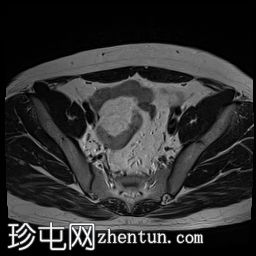

轴位

T2加权像

双侧睾丸均未在阴囊内显露,而是位于盆腔腹股沟管上部。

-左侧睾丸大小为2.6 cm x 1.6 cm x 2 cm。

-右侧睾丸大小为2.6 cm x 1.2 cm x 1.1 cm。

双侧隐睾(睾丸未降)位于盆腔腹股沟管上部。